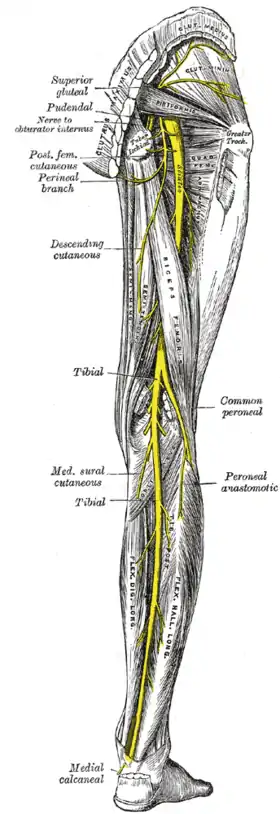

Nerve supply

The sensory and motor innervation to the lower limb is supplied by the lumbosacral plexus, which is formed by the ventral rami of the lumbar and sacral spinal nerves with additional contributions from the subcostal nerve (T12) and coccygeal nerve (Co1). Based on distribution and topography, the lumbosacral plexus is subdivided into the lumbar plexus (T12-L4) and the Sacral plexus (L5-S4); the latter is often further subdivided into the sciatic and pudendal plexuses:[45]

The nerves of the sacral plexus pass behind the hip joint to innervate the posterior part of the thigh, most of the lower leg, and the foot.[45] The superior (L4-S1) and inferior gluteal nerves (L5-S2) innervate the gluteus muscles and the tensor fasciae latae. The posterior femoral cutaneous nerve (S1-S3) contributes sensory branches to the skin on the posterior thigh.[48] The sciatic nerve (L4-S3), the largest and longest nerve in the human body, leaves the pelvis through the greater sciatic foramen. In the posterior thigh it first gives off branches to the short head of the biceps femoris and then divides into the tibial (L4-S3) and common fibular nerves (L4-S2). The fibular nerve continues down on the medial side of biceps femoris, winds around the fibular neck and enters the front of the lower leg. There it divides into a deep and a superficial terminal branch. The superficial branch supplies the fibularis muscles and the deep branch enters the extensor compartment; both branches reaches into the dorsal foot. In the thigh, the tibial nerve gives off branches to semitendinosus, semimembranosus, adductor magnus, and the long head of the biceps femoris. The nerve then runs straight down the back of the leg, through the popliteal fossa to supply the ankle flexors on the back of the lower leg and then continues down to supply all the muscles in the sole of the foot.[49] The pudendal (S2-S4) and coccygeal nerves (S5-Co2) supply the muscles of the pelvic floor and the surrounding skin.[50]